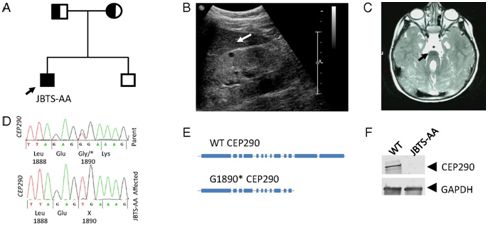

Joubert综合征(Joubertsyndrome)是一种脑部疾病,引起不同程度的身体和精神障碍,有时还引起视觉障碍。在新生儿中,这种疾病的发病率为1/80000,而且三分之一的患者也会遭受肾功能衰竭。并非所有的Joubert综合征患者都携带发生G1890*突变的CEP290基因,其中G1890*突变会导致肾脏遭受损伤。那些出现肾脏疾病的患者可能需要接受肾脏移植或透析

在一项新的研究中,英国纽卡斯尔大学遗传医学研究所的JohnSayer教授及其同事们在细胞模型和小鼠模型中,发现使用一条称为反义寡核苷酸(antisenseoligonucleotide,ASO)的DNA链可诱导患者细胞发生选择性剪接,跳过CEP290基因中发生G1890*突变的外显子41,这种方法称为“外显子跳读(exon-skipping)”。相关研究结果于2018年11月15日在线发表在PNAS期刊上,论文标题为“TargetedexonskippingofaCEP290mutationrescuesJoubertsyndromephenotypesinvitroandinamurinemodel”。